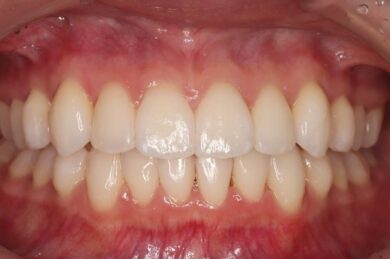

八重歯・叢生 マウスピース矯正(インビザライン)26歳女性 非抜歯

「前歯のガタガタ(叢生)と八重歯を治したい」を主訴に来院された患者様です。上下の歯にIPRを加え、歯列弓の拡大を行い、非抜歯で前歯のガタガタを整えました。顎間ゴムを用い、咬み合わせも改善されています。アライナーの装着時間が長く、チューイをしっかり使用していただけたため、非常に短時間で仕上がりました。

• 治療後